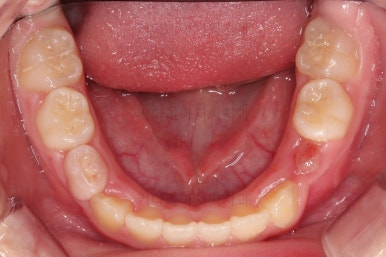

치료 22개월 째 종료시점의 사진입니다.

전후 비교해 볼게요.

교합도 좋아졌고 앞니 관계(반대교합, 개방교합)도 개선이 잘 되었어요.